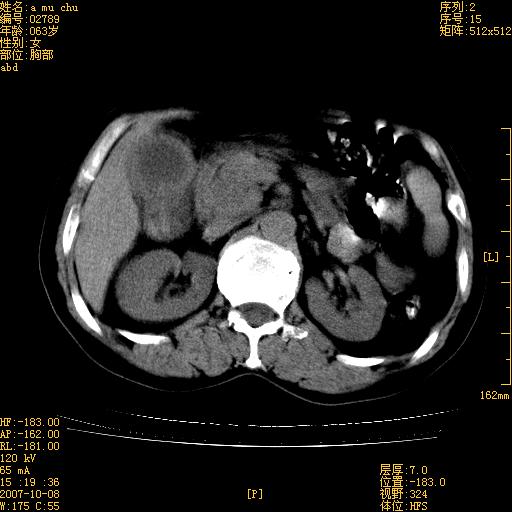

以下是引用王维浦在2007-10-17 21:02:00的发言:[br]胆囊增大,囊壁明显不规则增厚,邻近肝组织浸润,肝内外胆管无扩张。诊断:胆囊ca;[br]胰头软组织肿块影,考虑是由转移肿大的胰后淋巴结、没有肠道准备的十二指肠及胰头共同形成。[br]

以下是引用zhangzexing在2007-10-18 7:13:00的发言:[br]支持胰头占位,慢性胆囊炎. 2.肝左叶前外侧段占位,血管瘤?建议增强

以下是引用影像实习生在2007-10-17 19:49:00的发言:[br]支持胰头占位,慢性胆囊炎. 2.肝左叶前外侧段占位,血管瘤?建议增强.

以下是引用刘振江在2007-10-17 19:42:00的发言:[br]没有增强,胰头癌?胆囊及肝左叶占位?